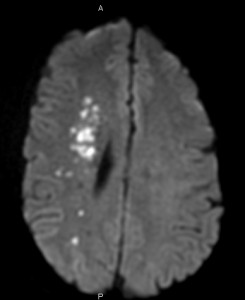

- Atheroembolism means that clots dislodge from fresh thrombus. As the artery occludes, a thrombus builds up above the occlusion (toward the head), up to the ophthalmic artery. If a piece of that thrombus dislodges (especially when this is fresh and not organized) it may cause transient ischemic attack (TIA) or stroke.

- Hypoperfusion means that the brain does not receive enough blood flow through the collaterals that were mentioned. If blood pressure is reduced, it may aggravate the hypoperfusion. The area that is most damaged is called the watershed. The watershed is the area of the brain on the border between blood supply of main cerebral arteries.